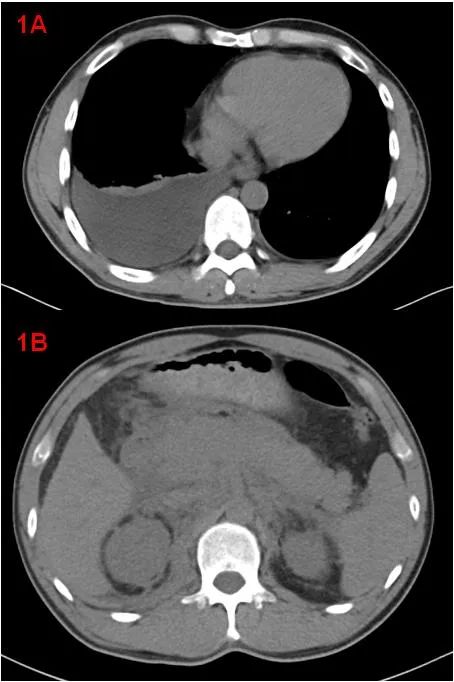

中年男性,體檢發(fā)現(xiàn)“雙腎積水”來診,余無明顯不適。CT示雙側胸腔積液、右肺膨脹不全(圖1A);胰腺腫大、胰周滲出,腹腔少量積液、腹膜、網膜增厚,腹膜后軟組織增厚(圖1B);考慮自身免疫性胰腺炎?腹膜后纖維化?